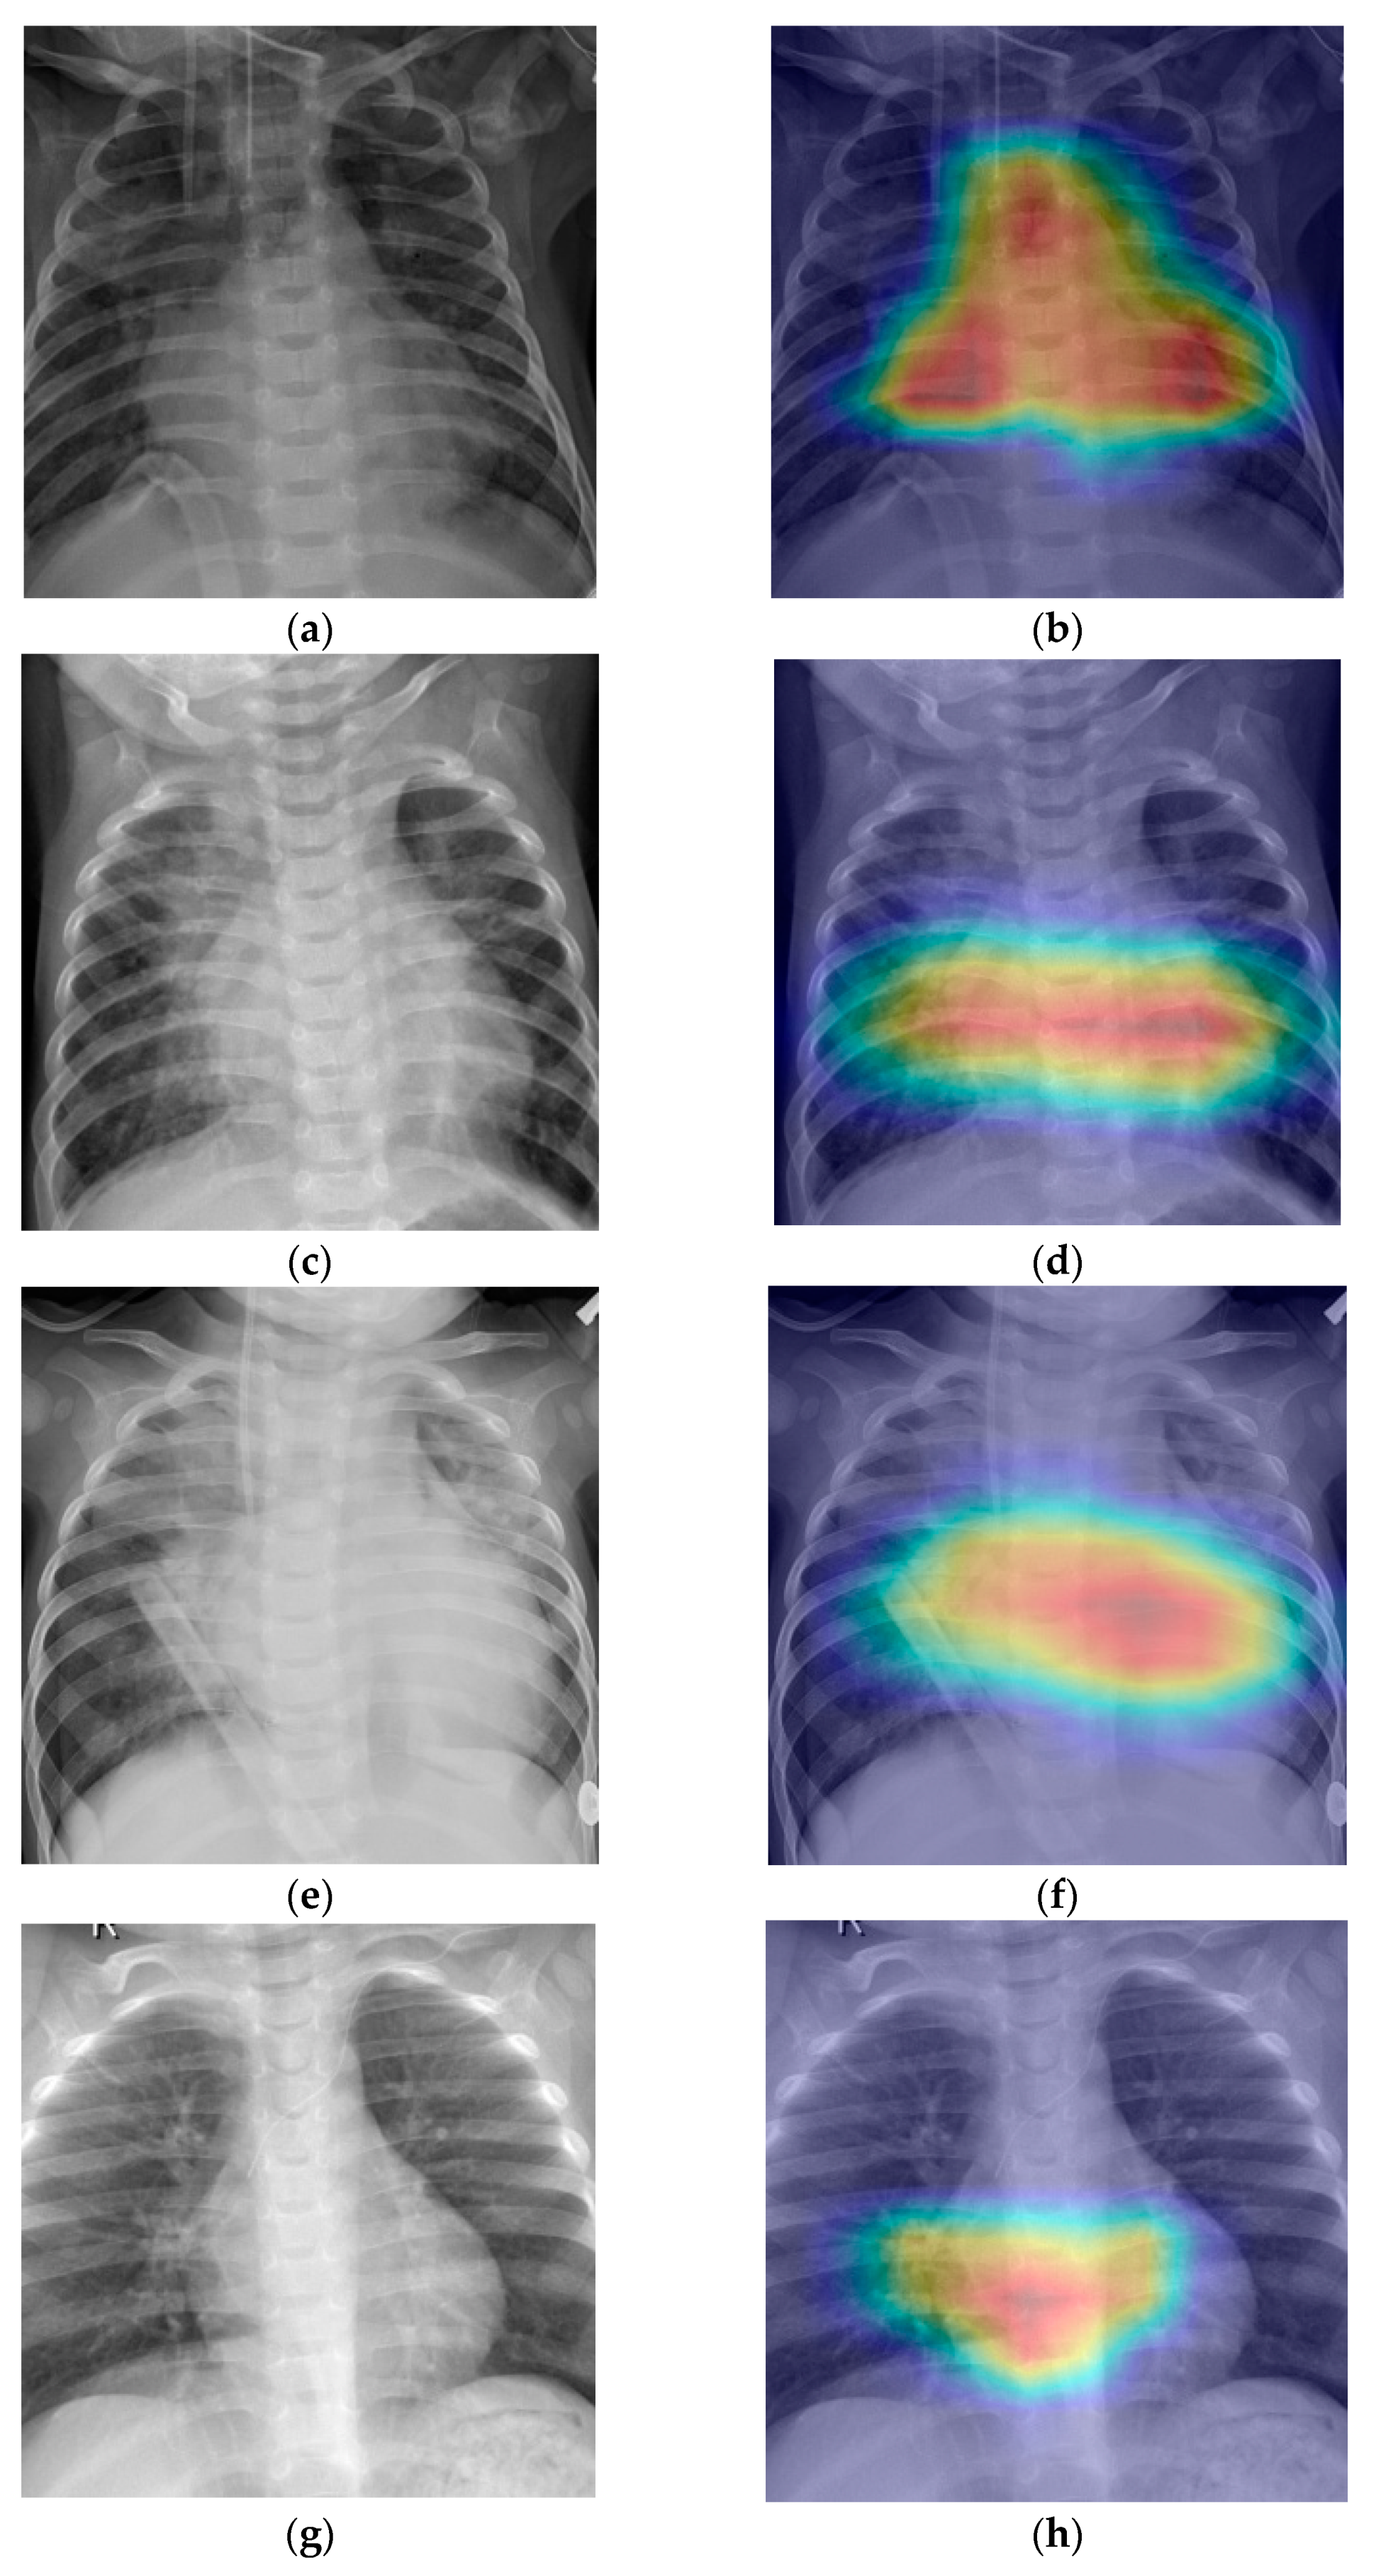

- Grad-CAM was used in order to generate a heatmap of the possible localization of pneumonia manifestations on test images.

6. Discussion

- Selvaraju, R.R.; Cogswell, M.; Das, A.; Vedantam, R.; Parikh, D.; Batra, D. Grad-CAM: Visual Explanations from Deep Networks via Gradient-based Localization. Int. J. Comput. Vis. 2020, 128, 336–359. [Google Scholar] [CrossRef]